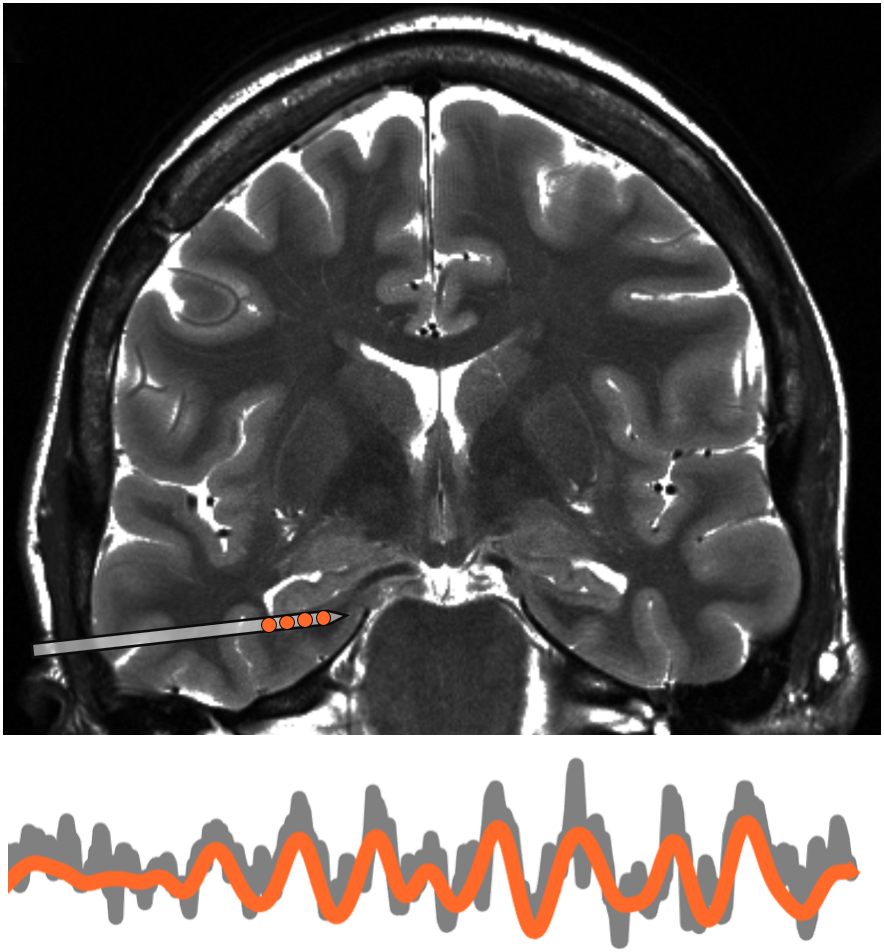

لاحظت سوذانا وزملاؤها مرضى الصرع الذين زُرعت بصورة جراحية أقطاب كهربائية في أدمغتهم في وقت سابق للسيطرة على النوبات التي يتعرضون لها. الأقطاب الكهربائية استقرت في الفص الصدغي الإنسي، وهو مركز الدماغ المرتبط بالذاكرة ويُشتبه في أنه ينظم حركة التنقل، مثل جهاز تحديد المواقع GPS.

تشير النقاط البرتقالية إلى النشاط الصادر من قطب كهربائي مزروع في الدماغ.

قال المؤلف الأول ماتياس ستانغل Matthias Stangl، باحث ما بعد الدكتوراه في مختبر سوذانا: ”أثبتت الدراسات السابقة أن موجات الدماغ منخفضة التردد الصادرة من الخلايا العصبية في الفص الصدغي الإنسي تساعد القوارض على تتبع مكان وجودها أثناء تنقلها في مكان جديد“. ”أردنا التحقيق في هذه الفكرة لدى الناس - وأن نفحص ما إذا كان بإمكانهم أيضًا رصد ناس آخرين بالقرب منهم - لكن التكنولوجيا الحالية أعاقتنا عن اكمال المهمة.“